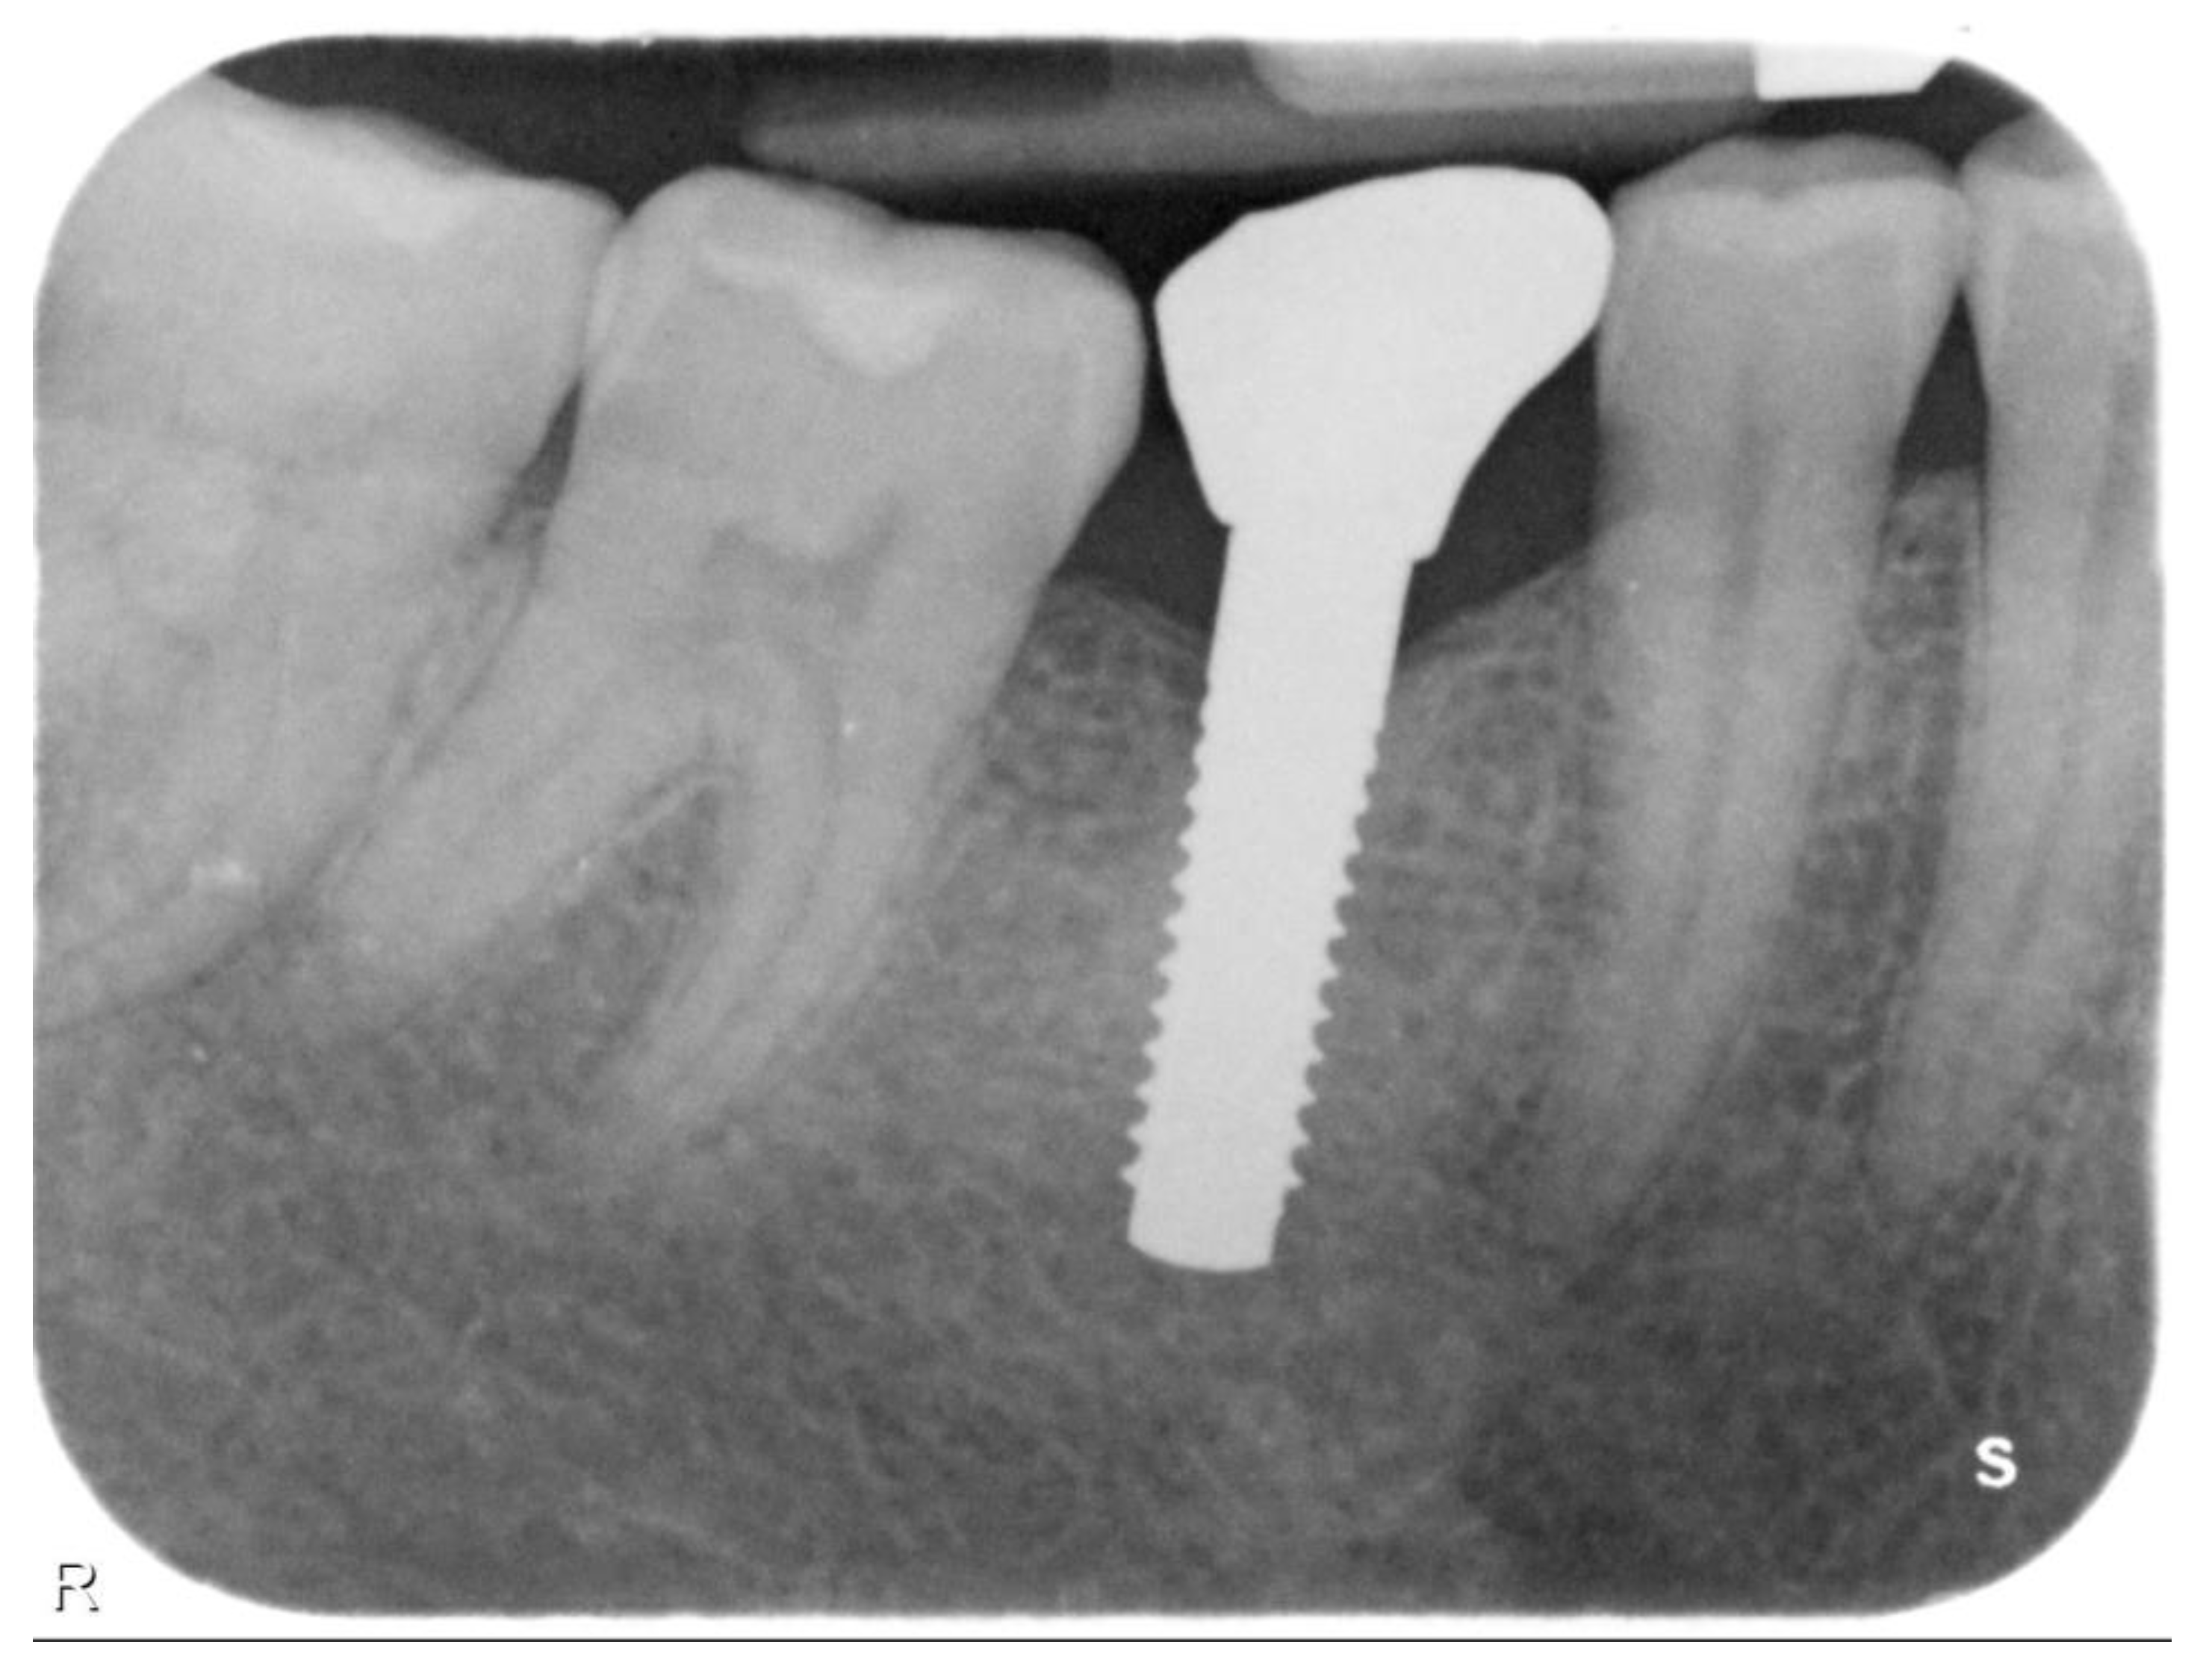

2. Materials and Methods

Implant Characteristics